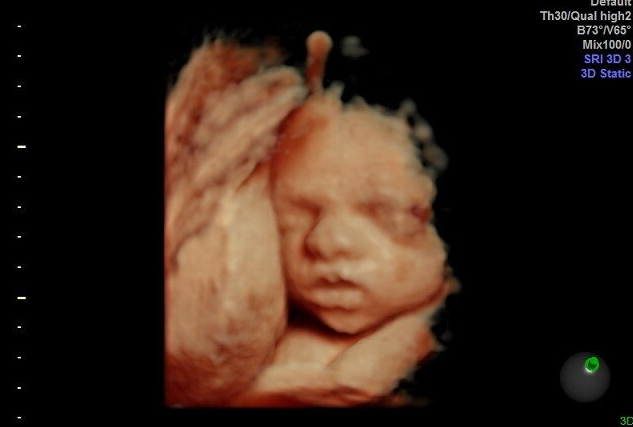

Gallery